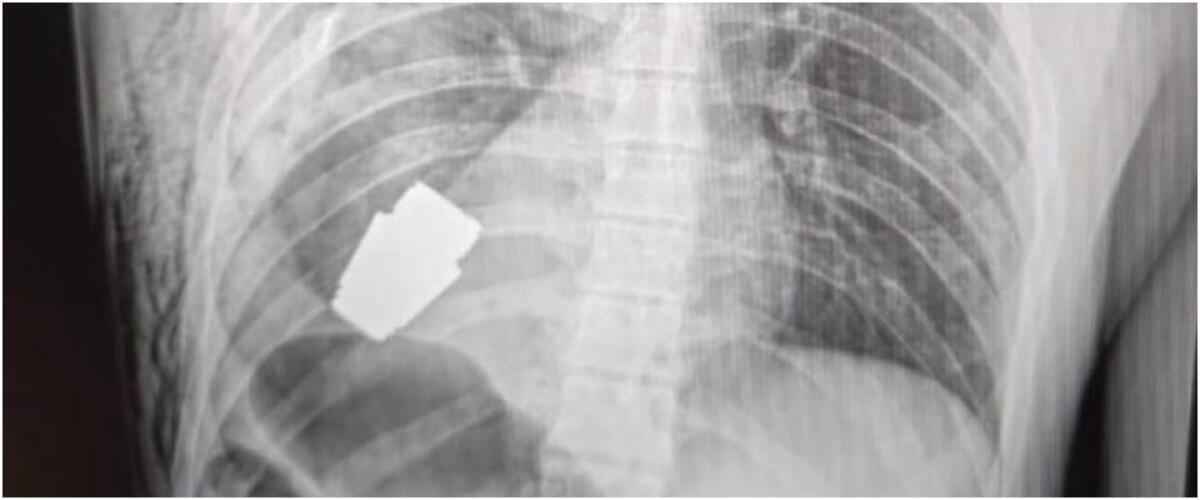

La vice ministra ha postato l'immagine di una radiografia in cui si vede l'ordigno all'interno del corpo del soldato e una foto di un chirurgo che osserva la granata dopo l'intervento.

La parte inesplosa della granata si trovava sotto il cuore del militare ferito, ha precisato Gerashchenko.